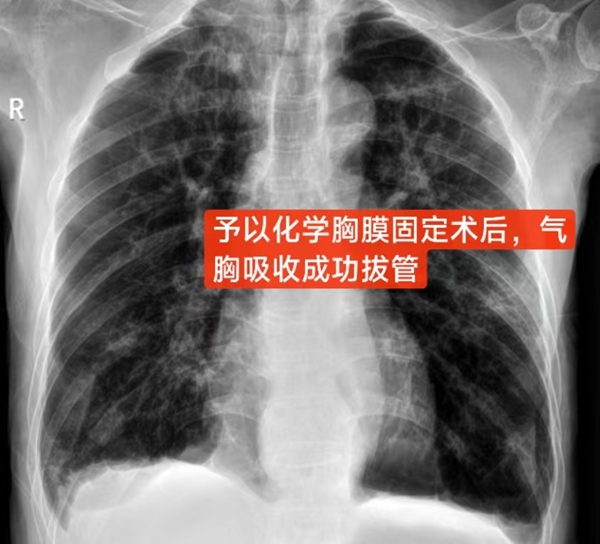

面对这一难题,呼吸与危重症医学科主任李儒鹏在详细了解彭爷爷的病情后,考虑其年纪大,肺功能很差,难以耐受外科手术治疗,于是提出了一种创新的治疗方法——化学性胸膜固定术。患者及其家属详细了解该治疗方案后,表示同意行化学胸膜固定术治疗难治性气胸。于是,在李儒鹏指导下,主治医生刘铁强为彭爷爷经胸腔闭式引流管注入了多西环素行化学胸膜固定术。经治疗,彭爷爷胸腔引流管连接水封瓶内的气泡逐渐减少,复查胸片右肺气胸基本吸收,最后成功拔出引流管,康复出院。出院后追踪随访,彭爷爷情况一直比较稳定,没有再气胸发作。